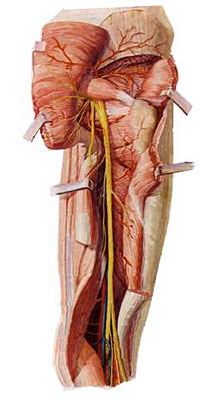

5. 5. 骶丛 Sacral plexus

由腰骶干、骶神经、尾神经前支组成。 By lumbosacral trunk, sacral nerve, nerve branches before the end of the composition. 位于盆腔侧壁,梨状肌前方。 Located in the pelvic sidewall, piriformis front. 主要分支有: The main branches are:

(3)坐骨神经 (3) the sciatic nerve

坐骨神经是全身最大的神经。 Sciatic nerve is the largest body. 于梨状肌下缘出骨盆,行于臀大肌深面,经坐骨结节与大转子连线的中点,下行至腘窝,分为胫神经和腓总神经。 At the lower edge of the pelvis piriformis, the line in the deep surface of the gluteus maximus, the midpoint of the greater trochanter and the ischial tuberosity through wiring, down to the popliteal fossa, into the tibial nerve and the common peroneal nerve. 坐骨神经本干布于髋关节和股肌后群。 The sciatic nerve with a dry cloth in the hip and thigh muscles after the group.

1)胫神经 1) tibial nerve

沿腘窝中线,经小腿后群肌深浅两层间下降,于内踝后方至足底分为足底内侧神经和足底外侧神经。 Popliteal fossa along the midline, after the calf muscle depth between the two groups decreased in the medial malleolus to the rear foot into the medial plantar nerve and lateral plantar nerves.

胫神经肌支支配小腿后群肌、足底肌。 Tibial nerve calf muscle branches after dominating muscle group, plantar muscles. 皮支布于膝关节、小腿后面皮肤、足底皮肤。 Cutaneous branches distributed in the knee, back calf skin, foot skin. 胫神经损伤后表现为足“勾状外翻”。 Posterior tibial nerve injury manifested as foot "hook-shaped valgus."

2)腓总神经 2) peroneal nerve

沿腘窝上外侧缘向外,绕腓骨胫,分为腓浅、腓深神经。 Popliteal fossa along the outer edge of the outward around the tibia fibula, into superficial peroneal, deep peroneal nerve. 腓浅神经肌支支配小腿外侧群肌,腓深神经肌支支配小腿前群肌。 Superficial peroneal nerve muscular branches dominated lateral leg muscle groups, deep peroneal nerve muscular branches dominated front leg muscle groups. 腓总神经损伤后表现为足下垂伴内翻(即“马蹄内翻”)。 Peroneal nerve injury manifested as foot drop with varus (ie "clubfoot").